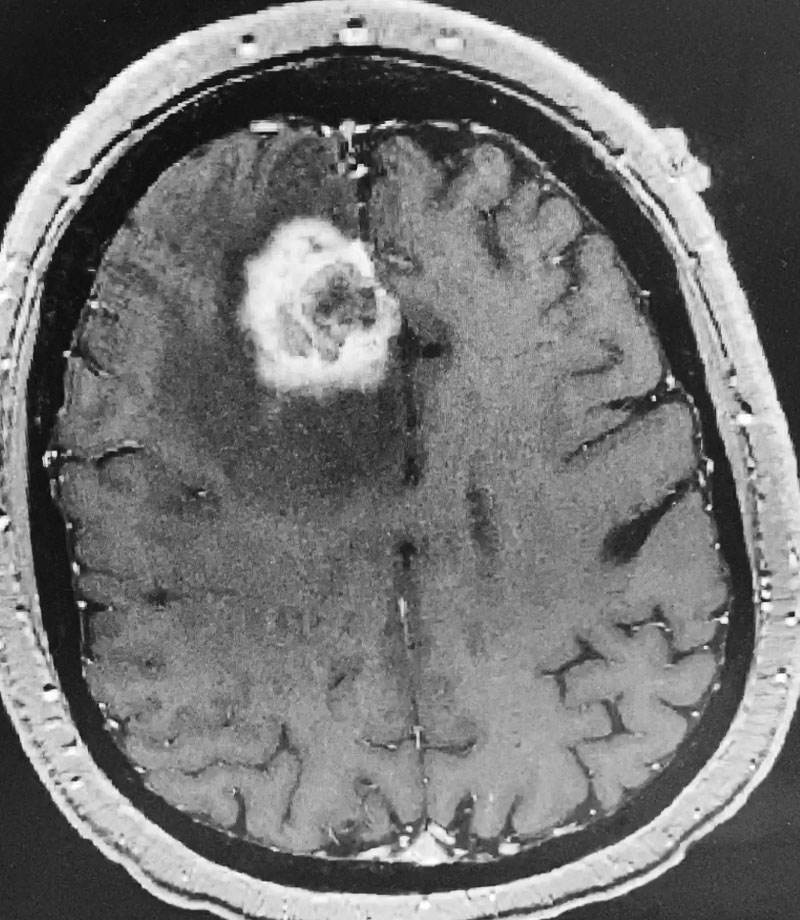

Postoperative images looked good (Figure 3). The patient felt better after surgery. His headaches were much better and he started to feel stronger. He was discharged after a brief hospital stay. He tapered his steroids to off. He will get follow up MRI images every few months. If tumor does recur, repeat radiosurgery would be performed.

Figure 3: Post operative CT scan.